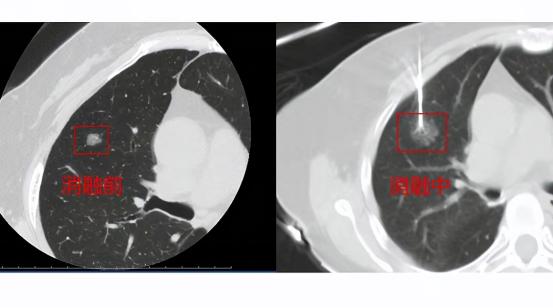

陈女士到肿瘤综合治疗中心进行诊治,请专家会诊后,考虑到患者的综合状况,决定给陈女士进行乳腺癌肺转移病灶氩氦刀冷冻消融术。

手术进行的很成功,冷冻效果很好,大约过了一星期,陈女士的身体症状明显好转,最后在休养下逐渐康复,出院前陈女士和女儿还特立向医院全体医务人员表示衷心的感谢!